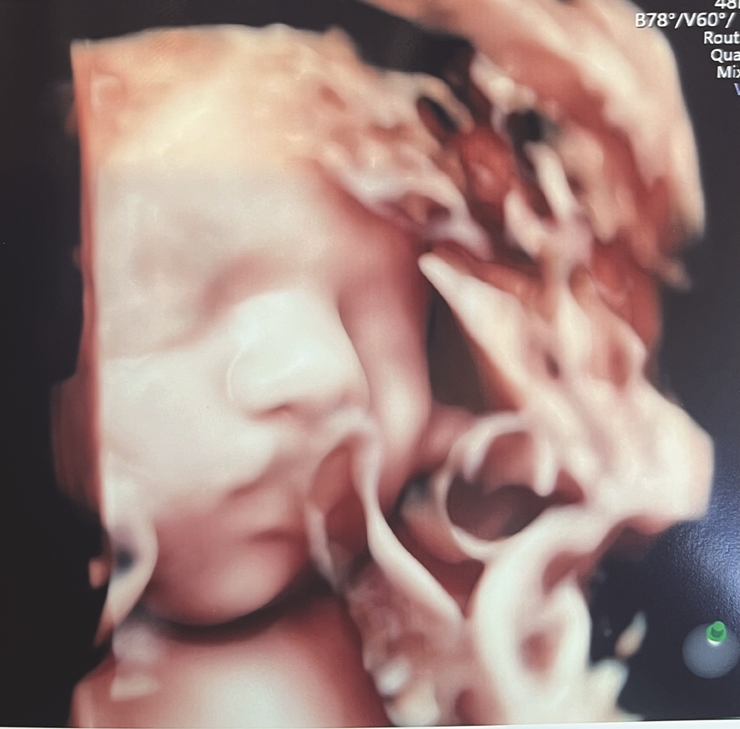

엄마 아빠는 지금 너를 만날 날을 손꼽아 기다리고 있단다. 너를 품에 안을 생각만 해도 마음이 따뜻해지고 눈가가 촉촉해지네. 엄마는 매일 너에게 예쁜 말만 들려주며, 건강하게 잘 자라길 바라고 있어.아가야, 세상으로 나오는 그 날까지 편안히 있다가 엄마 아빠의 사랑 가득한 품으로 무사히 와주렴. 너의 첫 울음소리를 기다리며, 엄마 아빠는 오늘도 너를 위해 기도하고 있어. 우리 아기, 사랑하고 또 사랑해.

서○○(경남 통영)